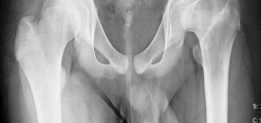

The hallmark pathoanatomy addressed by this procedure is coxa magna, characterized by an enlarged, often flattened, and extruded femoral head that results in hinge abduction and severe femoroacetabular impingement. Epidemiologically, the sequelae of childhood hip disorders present a significant burden, with untreated or severe Legg-Calvé-Perthes disease leading to premature osteoarthritis in the third or fourth decade of life. By surgically reducing the volume and reshaping the geometry of the deformed femoral head, orthopedic surgeons can re-establish a functional articulation within the native acetabulum. This conservative, albeit technically demanding, approach relies heavily on the principles of safe surgical dislocation of the hip, allowing for global access to the femoral head without compromising its tenuous vascular supply.

In the setting of coxa magna or severe cam deformity, the biomechanics of the hip are profoundly altered. The aspherical femoral head creates an abnormal center of rotation and leads to non-concentric articulation. During abduction, the enlarged lateral portion of the femoral head hinges against the lateral acetabular rim, a phenomenon known as hinge abduction. This hinging levers the medial femoral head out of the acetabulum, exponentially increasing contact pressures on the lateral compartment and leading to rapid articular cartilage degradation.

Radiographic evaluation must demonstrate a clear structural conflict, such as an extruded lateral head segment causing hinge abduction, but without advanced joint space narrowing. The presence of a "hinge" can often be confirmed dynamically under fluoroscopy or via abduction-internal rotation plain radiographs.

Standard radiographic series should include an anteroposterior pelvis, cross-table lateral, and false profile views of the affected hip. Functional views, such as maximum abduction and adduction radiographs, help quantify the degree of hinge abduction and the potential for concentric reduction.